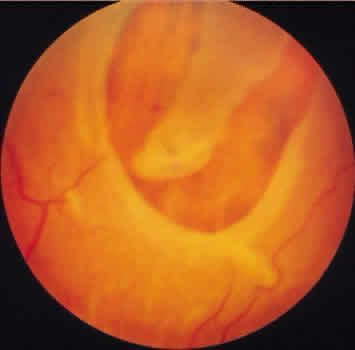

Retinoschisis associated with a bullous architecture and prominent reticular cystoid degeneration has been termed reticular degenerative retinoschisis. Reticular degenerative retinoschisis can be distinguished from typical degenerative retinoschisis by the large extent of retinal involvement, a round or ovoid configuration with bullous elevation of the extremely thin inner layer, and an irregular, pitted outer layer (Figs. 20 and 21). Typical cystoid degeneration is always present anterior to the schisis; reticular cystoid degeneration is usually prominent at some site in the involved eye. Blood vessels coursing through the inner layer give it an arborizing reticular pattern on contact lens biomicroscopy. The intraretinal cavity is optically empty; the outer wall is irregularly excavated to produce a pocked or honeycomb appearance. Round or ovoid holes are often present in the outer retinal layer; they are single or multiple, frequently large, and usually associated with a rolled posterior edge.13

Fig. 20. Reticular degenerative retinoschisis. Note reticulated, highly elevated, inner wall with a conspicuous delicate vascular pattern. Radial columns of the retina are completely disrupted within the region of bullous elevation, and the retinoschisis extends posterior to the equator. (× 18.)

Fig. 21. Clinical appearance of reticulardegenerative retinoschisis: diagram of involved area and photographs of ocular fundus showing optic disc, macula, and posterior portion of the schisis. These illustrate outer layer retinal breaks, adjacent retinal pigment epithelium abnormality, and a lo-calized nonrhegmatogenous retinal detach-ment.